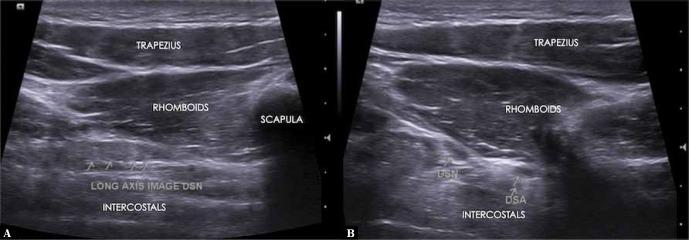

There are myriad causes for upper thoracic and interscapular pain which include pathologies involving the thoracic spine, costovertebral joints, facet joints and muscles (rhomboids and levator scapulae). Dorsal scapular nerve entrapment and the resulting neuropathy is a rare case of upper thoracic and medial scapular pain. The symptoms of dorsal scapular nerve entrapment neuropathy can be similar to other pathologies mentioned above. We report a rare case of dorsal scapular nerve entrapment managed successfully by ultrasound-guided hydrodissection, and describe the technique for the same. Awareness of this rare entity is advised while evaluating upper thoracic and interscapular pain.

上胸部和肩胛间疼痛有多种原因,包括涉及胸椎、肋椎关节、小关节和肌肉(菱形肌和肩胛提肌)的病变。肩胛背神经卡压及由此导致的神经病变是上胸部和肩胛内侧疼痛的罕见病例。肩胛背神经卡压性神经病变的症状可能与上述其他病变相似。我们报告一例通过超声引导下水分离术成功治疗的肩胛背神经卡压罕见病例,并描述了该技术。在评估上胸部和肩胛间疼痛时,建议了解这种罕见情况。